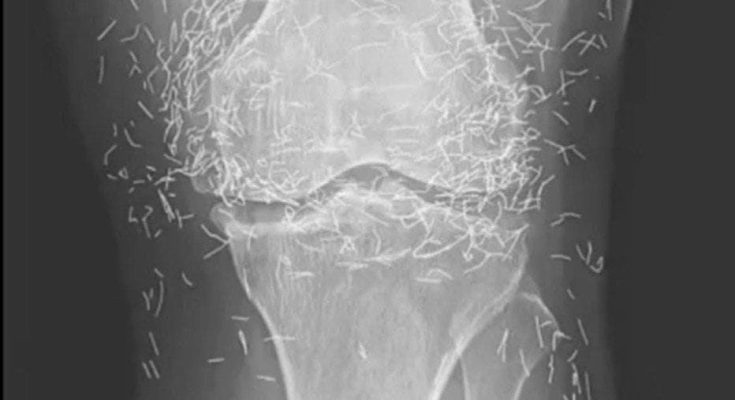

Years later, when doctors took X-rays to evaluate her knee condition, they weren’t prepared for what appeared on the images. Her knees were filled with dozens of bright, metallic flecks — tiny needles embedded deep within the joint area.

The findings were later documented in a case published by the New England Journal of Medicine.

Beyond inflammation, the needles created another problem: imaging complications. Metal objects can obscure parts of the anatomy on X-rays, making it harder for doctors to clearly assess joint damage or disease progression.

Even more concerning, the presence of metal inside the body can make certain scans dangerous. MRI machines rely on powerful magnetic fields, and embedded needles may shift during scanning, potentially damaging blood vessels or surrounding tissue. In short, future diagnostic options for this patient became limited.